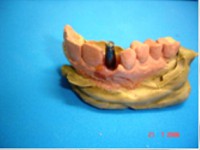

Carga Imediata após exodontia atraumática

- Implante imediato

- Carga imediata

- Aplicação da cerâmica de baixa fusão direto sobre o pilar